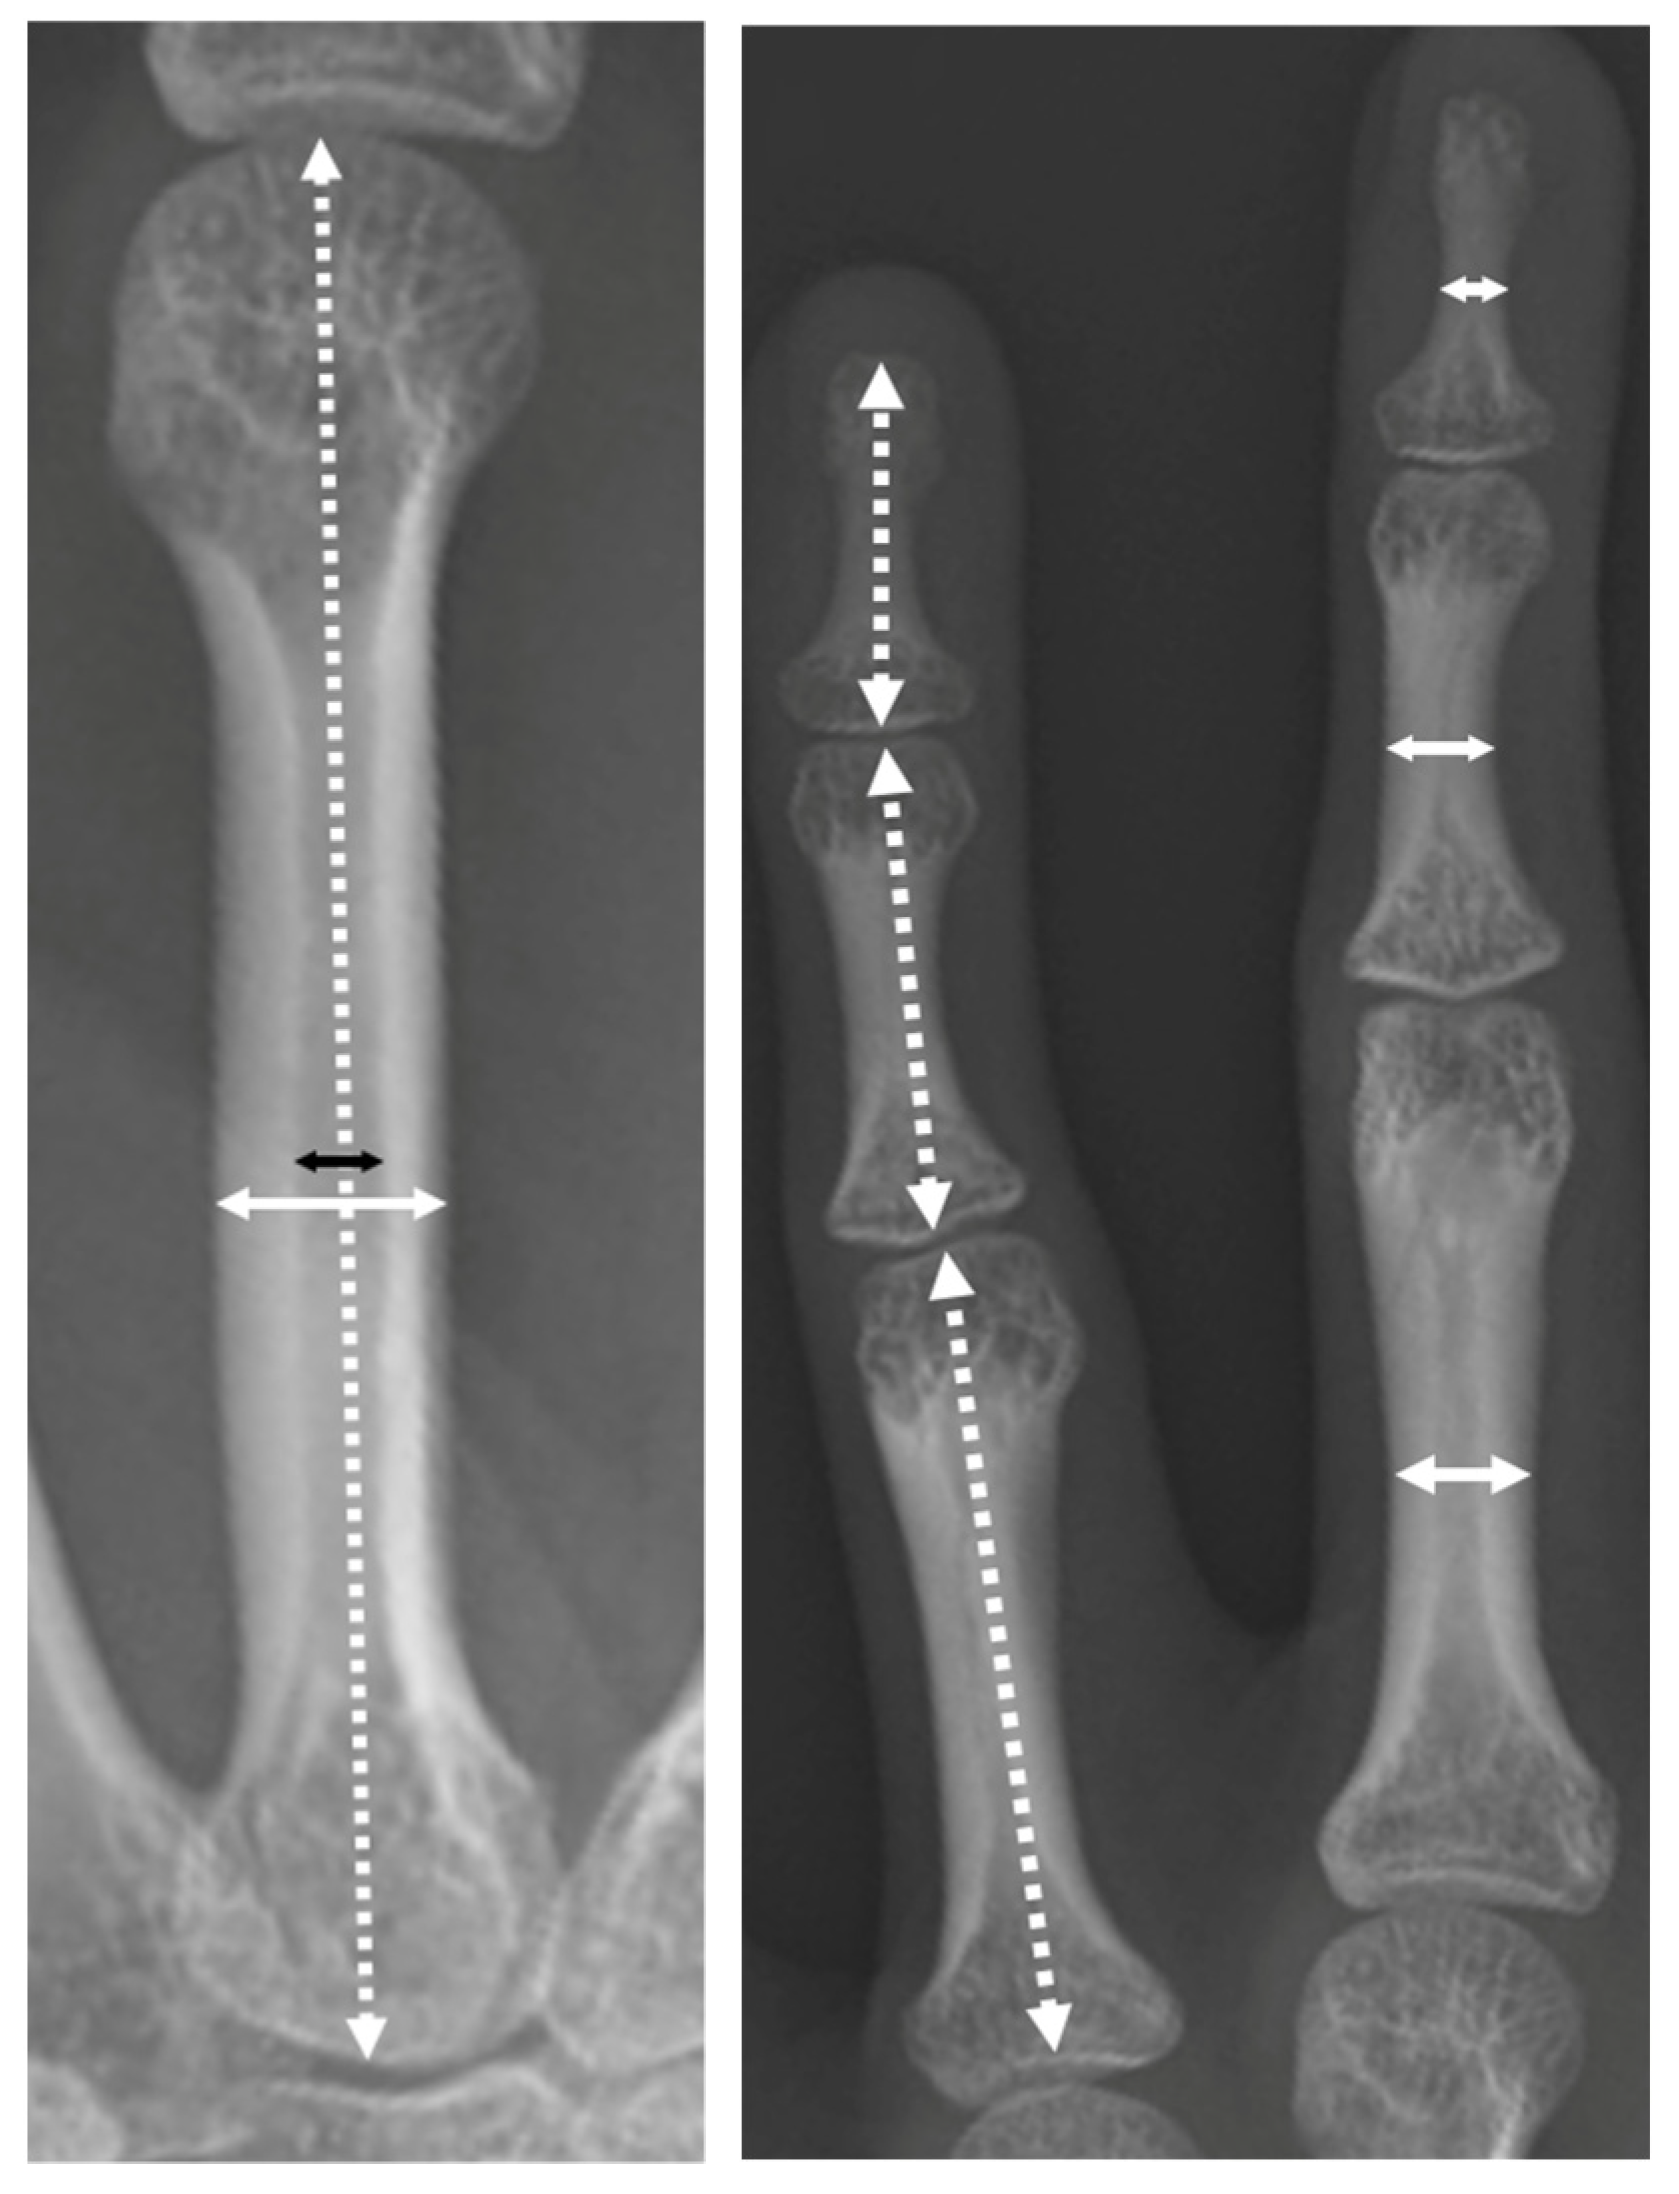

The length and width of each phalanx and metacarpal bone and the width of the third metacarpal medullary cavity were measured on posteroanterior radiographs of the hand, and the ratio of the medullary cavity of the metacarpal bone was measured (width of medullary cavity/metacarpal) and calculated (Figure 3).

Figure 3.

The two-headed arrows of the white dotted line indicate the length of the metacarpal bones and distal, middle, and proximal phalanges. The two-headed arrows of the white solid line indicate the width of the metacarpal bones and distal, middle, and proximal phalanges. The black two-headed arrows indicate the width of the third metacarpal medullary cavity.

The phalanges and metacarpals are thin, and the ratio of medullary cavity of the metacarpal bone decreases with age (Table 4 and Table 5).